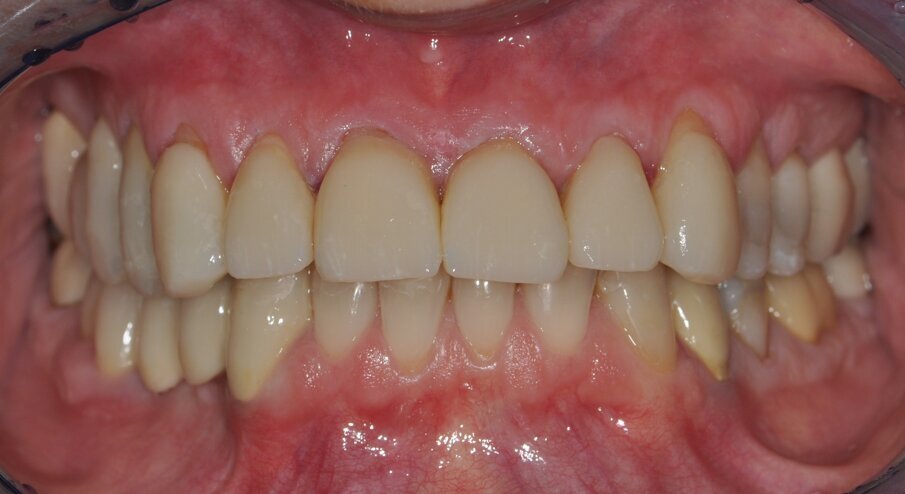

Figs. 13 and 14: Final restorative result after adhesive cementing

Fig. 16: Postoperative smile and lip profile

Calibra dual-curing resin cement (Dentsply Sirona Restorative) was used for adhesively cementing the full and partial crowns. The veneers were used with a light-curing cement (Calibra Esthetic Resin Cement, Dentsply Sirona Restorative). After thorough removal of any excess resin and light curing, the occlusion was checked and the restorations were polished (Figs. 13 and 14).The zirconia-reinforced lithium silicate ceramics are characterized by good polishability and shade adaptation to neighboring structures (Figs. 15 and 16).